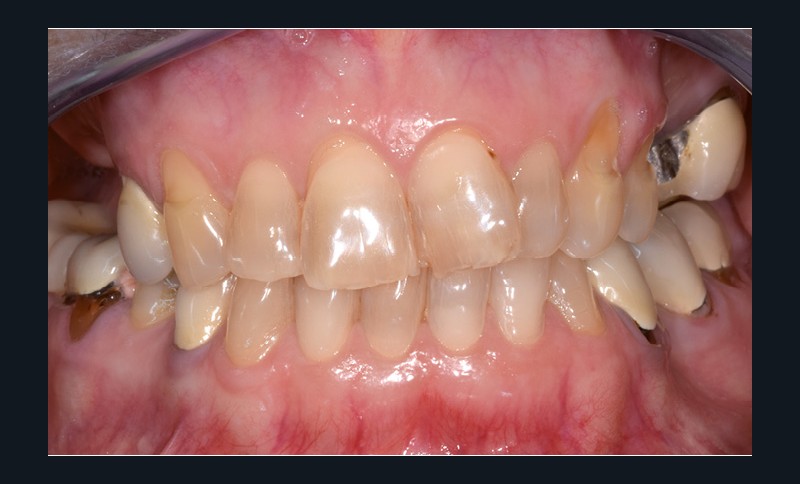

Une patiente d’une cinquantaine d’années consulte pour refaire sa prothèse amovible partielle métallique maxillaire, source d’inconfort (fig. 1 et 2).

Nous sommes en présence, au maxillaire, d’un édentement de classe 2 subdivision 1 de moyenne étendue (fig. 3). La problématique propre à ce cas de classe 2 est le soulèvement lors de la mastication d’aliments mous/collants et l’asymétrie. Cependant, la présence d’une subdivision compense en partie l’asymétrie. La recherche d’appuis les plus antérieurs possible à l’axe de rotation pour contrer le mouvement de soulèvement postérieur est également…